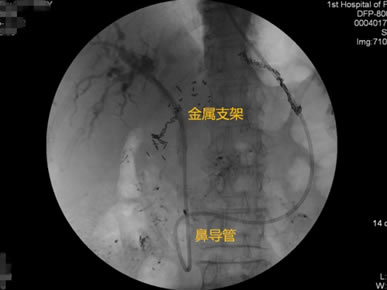

胃毕-Ⅱ术后乳头倒置 胃毕-Ⅱ术后胰管胆管双支架植入 胃毕-Ⅱ术后金属支架植入

胃毕-Ⅱ术后肝门部胆管狭窄 胃毕-Ⅱ术后金属支架植入